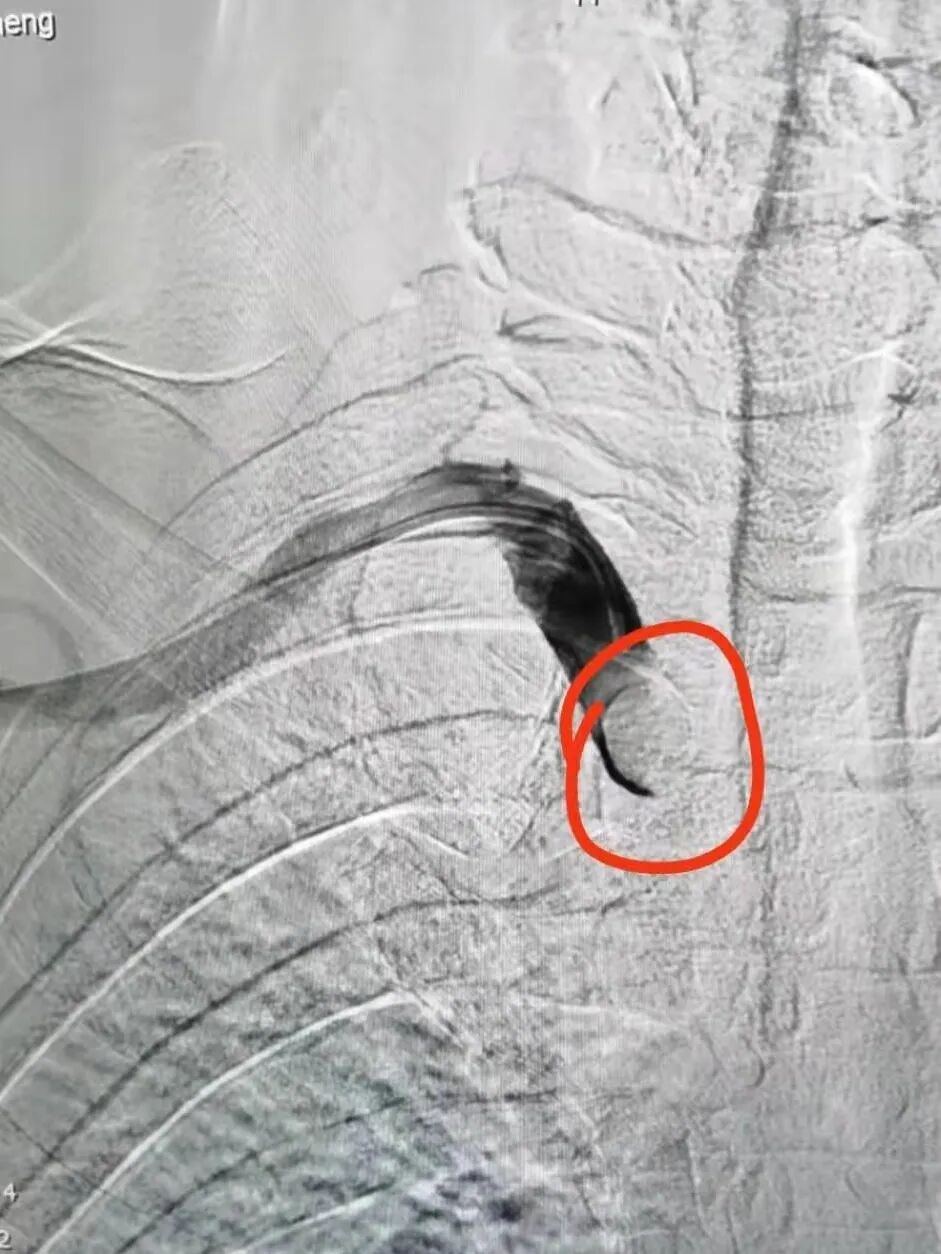

在征得王先生及家人同意后,魏主任组织介入团队进行术前讨论,依据患者病情拟定了详细的手术方案,手术由魏主任亲自操作,在手术中意想不到的遇到了重重困难:一是斑块硬开通困难,二是斑块脱落形成栓塞,三是病灶在夹层,四是支架不能堵塞椎动脉等,给手术带来很大风险,凭借多年的临床实践,终于把血管开通、支架植入。后经造影显示:右锁骨下动脉支架置入后恢复前向血流,不再盗血,手术历时4个小时,整个过程可谓“惊心动魄”。